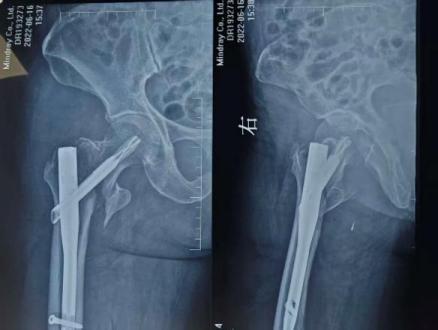

第一次内固定术后X线片及CT

此次入院前X线片及CT

怀着最后一线希望,谈大妈与家属慕名来到陕西省核工业二一五医院创伤骨科寻求诊治。吴超副主任医师接诊后,立即为谈大妈安排了详细且全面的检查,经影像检查发现,虽然粗隆间骨折已愈合,但此前植入的部分内固定物竟突破了股骨头、侵入髋臼,导致股骨头已坏死变形、髋臼骨质缺损。